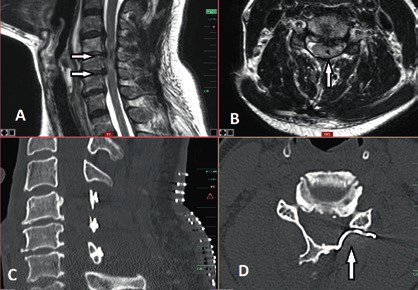

Prinzipiell richtet sich die Entscheidung, welche operative Versorgung durchgeführt wird, nach Ausmaß und Art der Verletzung. Für die Stabilisierung der dorsalen Säule reicht im Falle einer stabilen ventralen Säule die dorsale Instrumentierung aus. Hier gewährleisten dorsale Pedikelschrauben, die mit einem Stab verbunden sind, eine gute Wiederherstellung der Stabilität (Abb. 2). Im Falle einer instabilen ventralen Säule ist hingegen eine Implantation von Wirbelkörperersatz und eine dorsoventrale Segmentversteifung indiziert (Abb. 3). Die entwickelten minimalinvasiven Techniken – zum Beispiel die transkutane Pedikelschraubenimplantation oder der Wirbelkörperersatz durch endoskopische Thorakotomie – haben dazu geführt, dass das Wundgebiet und die operationsbedingte Gewebeschädigung reduziert werden und somit eine Belastungsreduktion für den Körper erzielt wird. Dieser Aspekt ist insbesondere bei älteren Patienten mit multiplen Begleiterkrankungen von Vorteil. Im Falle einer osteoporotischen Wirbelsäule werden die implantierten Pedikelschrauben zementiert (Abb. 4). Auch hier erlaubt die Entwicklung fenestrierter Schrauben eine optimale Möglichkeit der Zementapplikation.

Die operative Therapie ist unabdingbar im Falle von Wirbelsäuleninstabilität und/oder Rückenmarkkompression mit progredienter inkompletter Querschnittsymptomatik. In diesen Fällen besteht ein breiter Konsens, dass die operative Versorgung bei älteren Patienten eine dringende Indikation und in den Fällen sukzessiver neurologischer Verschlechterung eine Notfallindikation darstellt. Dagegen ist es bei der Indikationsstellung zur operativen Therapie bei stabilen, jedoch degenerativen Wirbelsäulen mit posttraumatischen Querschnittverletzungen schwieriger, einen Konsens zu finden 14 15. In diesen Fällen ist die Evaluation der potenziellen Vorteile einer Dekompression der neuralen Strukturen entscheidend für die Indikationsstellung einer operativen Therapie. Die Dynamik des posttraumatischen neurologischen Status spielt hier die entscheidende Rolle in der Evaluation. So werden Patienten mit komprimierender Spinalkanalstenose und zunehmender neurologischer posttraumatischer Verschlechterung von einer Dekompression des Spinalkanals mit großer Wahrscheinlichkeit profitieren (Abb. 6). Auch wenn die neurologische Erholung des Rückenmarks ungewiss bleibt, entfernt eine ausreichende Dekompression die schädigungsbegünstigende Ursache und beendet in den meisten Fällen die Verschlechterungsdynamik. Auch in den Fällen, in denen eine komplette Querschnittläsion besteht, kann die Dekompression perfusionsbedingte Sekundärschäden verhindern.